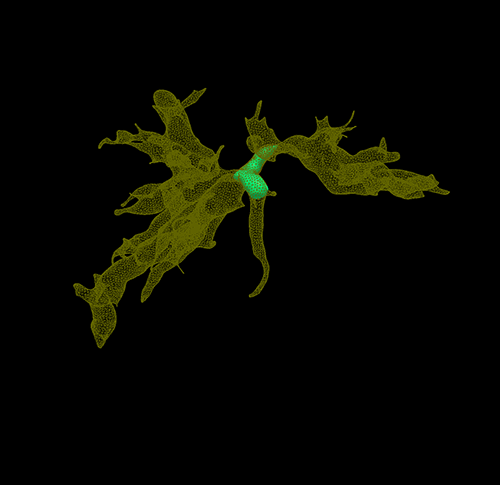

IV型胆管癌---胆管癌根治(左半肝+尾状叶切除)